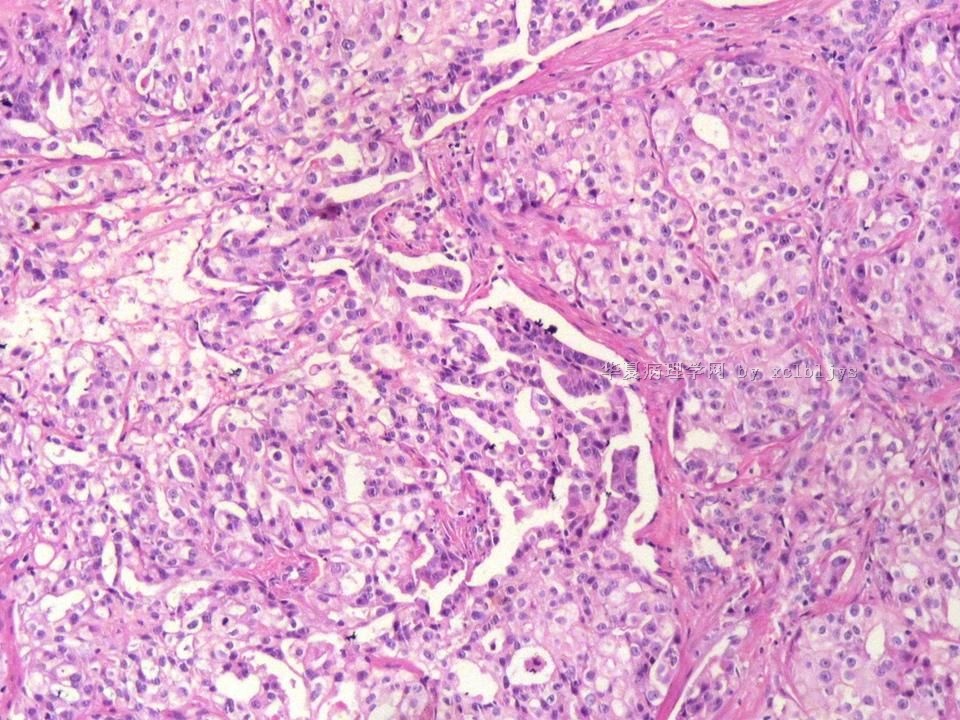

姓    名: ××× 性别:  男 年龄:  56

左锁骨上肿块三月余,手术切除。

蚕豆大肿块,包膜较完整,切面灰红色,质软。

• 左锁骨上肿块(IHC)图4

图4

免疫组化结果:TTF-1(+),CK7(+),CK20(-),TG(-)。临床近一步检查,肺未见肿块,左甲状腺发现肿块,目前仍未处理。

从形态结构看,有腺泡也有乳头结构,倾向转移性肺腺癌。